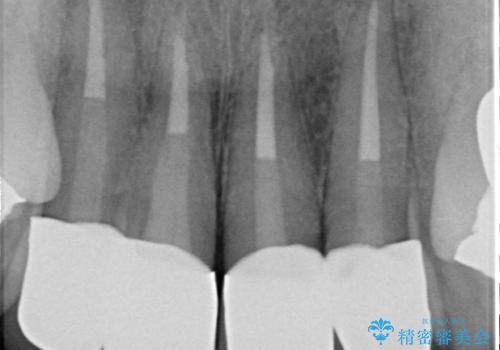

以前に治療した前歯クラウンは月日が経過することで劣化・歯肉の位置変化を引き起こし審美障害を引き起こしています。

劣化したクラウンを除去し、再発した虫歯を徹底的に除去したのち根管治療・ファイバーコア築盛を行いジルコニアクラウン製作へと移ります。

- 52万円(仮歯・ファイバーコア・ジルコニアクラウン×4)費用は治療当時の料金となります